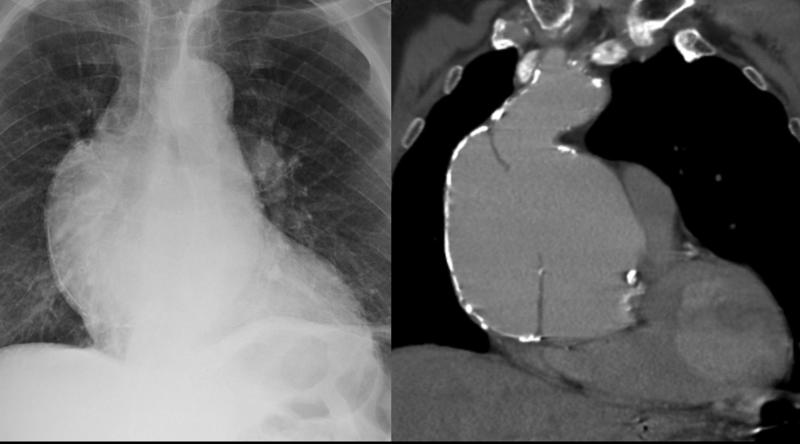

Aortic aneurysm